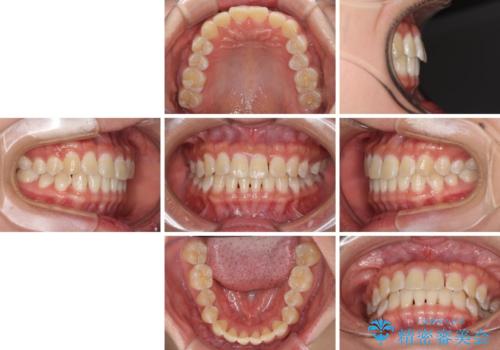

前歯の隙間と上下正中のズレを解消

- 上下前歯隙間と正中のズレを改善したいとのことで来院された患者様です。

自己管理を減らしたいとのことで、ワイヤー装置による矯正治療を行うこととしました。

正中がなかなか合わずに、2年近くの治療期間を要しました。